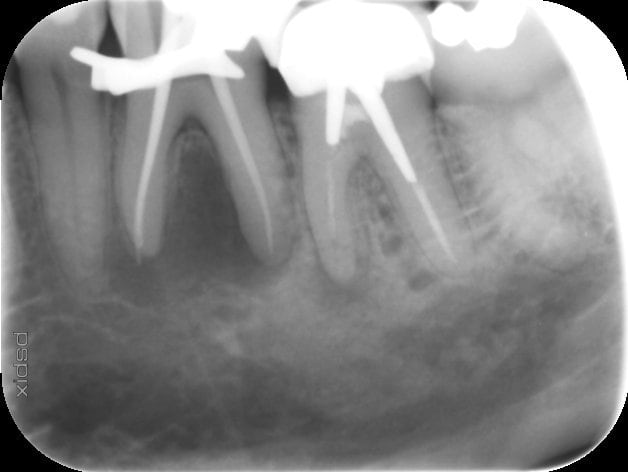

2ème cas plus particulier. La 36 présente une lésion interradiculaire énorme.

Je me demande ce qui a pu provoquer une telle lésion?

La dent est légèrement égressée.

Y a t il pu y avoir un trauma du fait de la perturbation occlusale (désolé pas de pano mais bridge avec courbe occlusale non harmonieuse en antagoniste).

Je compte tenter le traitement radiculaire de cette 36 qui réagit toujours au froid. Pas de douleurs à la percussion.

Je me demande s'il pourrait y avoir une fracture radiculaire ou est ce ''seulement'' une lésion endo paro?

36 lésion d'origine endo sans doute, test de vitalité ?

La molaire est peut être nécrosée partiellement. La radio est un peu cadrée serrée pour voir le contexte. De toute manière,tu verras bien faisant le traitement canalaire.

Vous pensez que la 36 peut cicatriser?

Ca me parait fort peu probable. As tu realisé un test de vitalité sur la 35?

A moins d'une fêlure radiculaire, la 36 a de grandes chances de cicatriser puisque les canaux sont larges et qu'il n'y a eu aucun traitement avant. Evidemment, il faut faire le travail correctement.

profites en pour reprendre la 37, y'a une pêche.

Fais un bon traitement de racine sur la 36, puis un composite. Contrôle régulièrement la cicatrisation. A mon avis tu peux t'attendre à un bon résultat. Au pire si échec tu auras recréé un environnement sain pour la pose d'un implant.